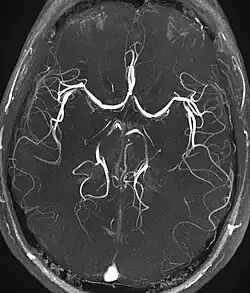

Angiografia metodą rezonansu magnetycznego[a], angiografia rezonansem magnetycznym, MRA (od ang. magnetic resonance angiography) – technika obrazowania metodą rezonansu magnetycznego służąca do nieinwazyjnej wizualizacji naczyń krwionośnych. Podstawowymi jej odmianami są angiografia czasu przepływu (TOF, od time of flight) i angiografia kontrastu fazy (PC, od phase contrast).

W tej metodzie, poprzez odpowiedni dobór sekwencji pomiarowej i czasów relaksacji, możliwe jest wzmocnienie sygnału pochodzącego od przepływającej krwi. Jednocześnie osłabiana jest intensywność sygnału od tkanek niebędących w ruchu.

Wykorzystuje się fakt, że protony tkanek znajdujących się w ruchu charakteryzują się przesunięciem fazowym. W tej technice otrzymuje się mapy przepływu krwi. Intensywność obrazu zależy od prędkości przepływu.